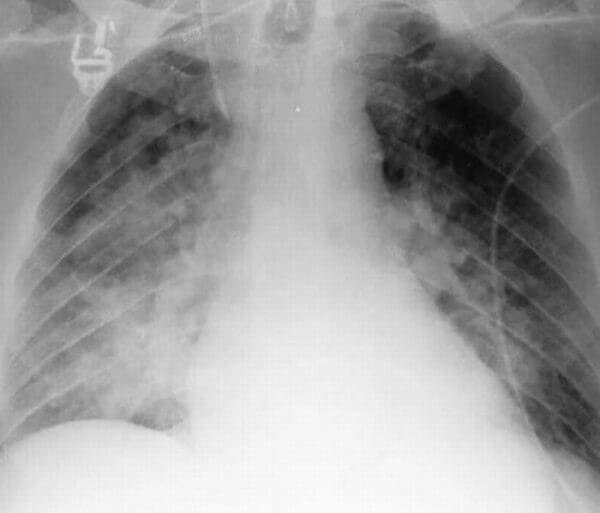

При абсцедирующей пневмонии на снимке отчетливо видно тотальное затемнение области инфильтрации и уплотнение плевры; наблюдаются полости до 2 см, в которых скапливается гнойная жидкость.

Фотоснимок при абсцедирующей пневмонии

- Абсцедирующая пневмония. Проявляется обширным затемнением пораженной области, признаками утолщения плевры и наличием полостей разного размера, наполненных жидкостью.